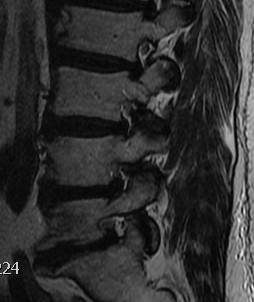

MRI

T2 Sagittal "MRI Myelogram"

B. Axial slices

Findings

- no fat about dura

- trefoil shape canal

- lateral recess or foramina compression

- nerve root compression